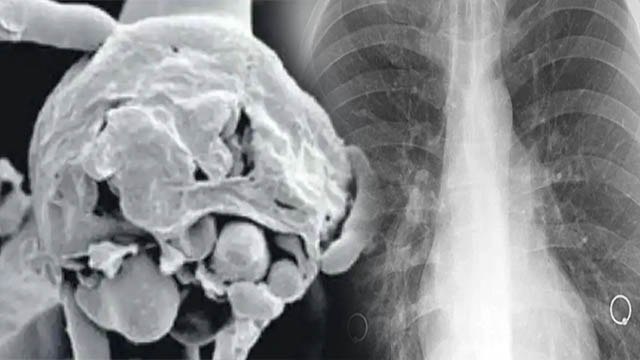

Buy Zetaclear – Nail Fungus Symptoms video tutorials is brought to you by healthandbeautyproductsreviews.com/

Zetaclear, Nail, Fungus, Symptoms